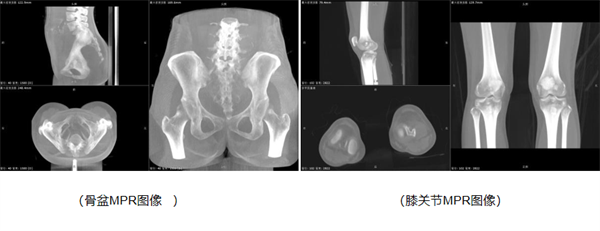

而立位锥束容积成像f-DR技术的出现,彻底颠覆了这一现状。该技术实现了在DR平台上的三维扫描与重建,能够全方位、多角度地呈现组织的冠状面、矢状面及横断面信息,使得诊断信息更加丰富、全面且精准。通过获取三维角度的扫描参数,该技术相较于传统的二维平片,无疑在数据的全面性和精准度上迈出了坚实的一步。

此外,立位锥束容积成像f-DR还具备独特的优势,它能够在患者站立位状态下,提供脊柱Cobb角、椎体旋转角、下肢力线等关键参数,为临床医生的诊断提供了极大的便利,显著提升了诊断效率。